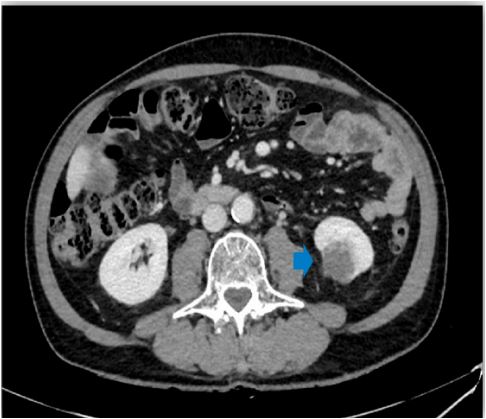

A Computed Tomography (CT) scan was ordered, which showed a 3 cm solid lesion in the left lower renal pole (Figure 1), multiple bony blasts at the dorsal, lumbar, and sacral levels, and a left adrenal lesion suggestive of metastasis (Figure 2). A brain Magnetic Resonance Imaging (MRI) was performed to complete the study and showed a right frontal lesion suggestive of metastasis.

Figure 1: CT image, a 3 cm solid lesion in the left lower renal pole.

Figure 2: MRI image, dorsal vertebral metastases.